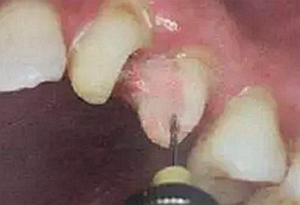

(干燥預(yù)備根管)

這樣容易破壞根管的牙本質(zhì)結(jié)構(gòu),也可形成較厚的玷污層,影響樹脂水門汀與牙體組織的粘接。

(沖洗預(yù)備根管)

應(yīng)選擇沖洗預(yù)備根管,防止牙膠及封閉劑粘連附著于根管壁形成第二層玷污層(根管治療時(shí)形成的玷污層稱為第一玷污層),利于樹脂水門汀與根管牙本質(zhì)的粘接。